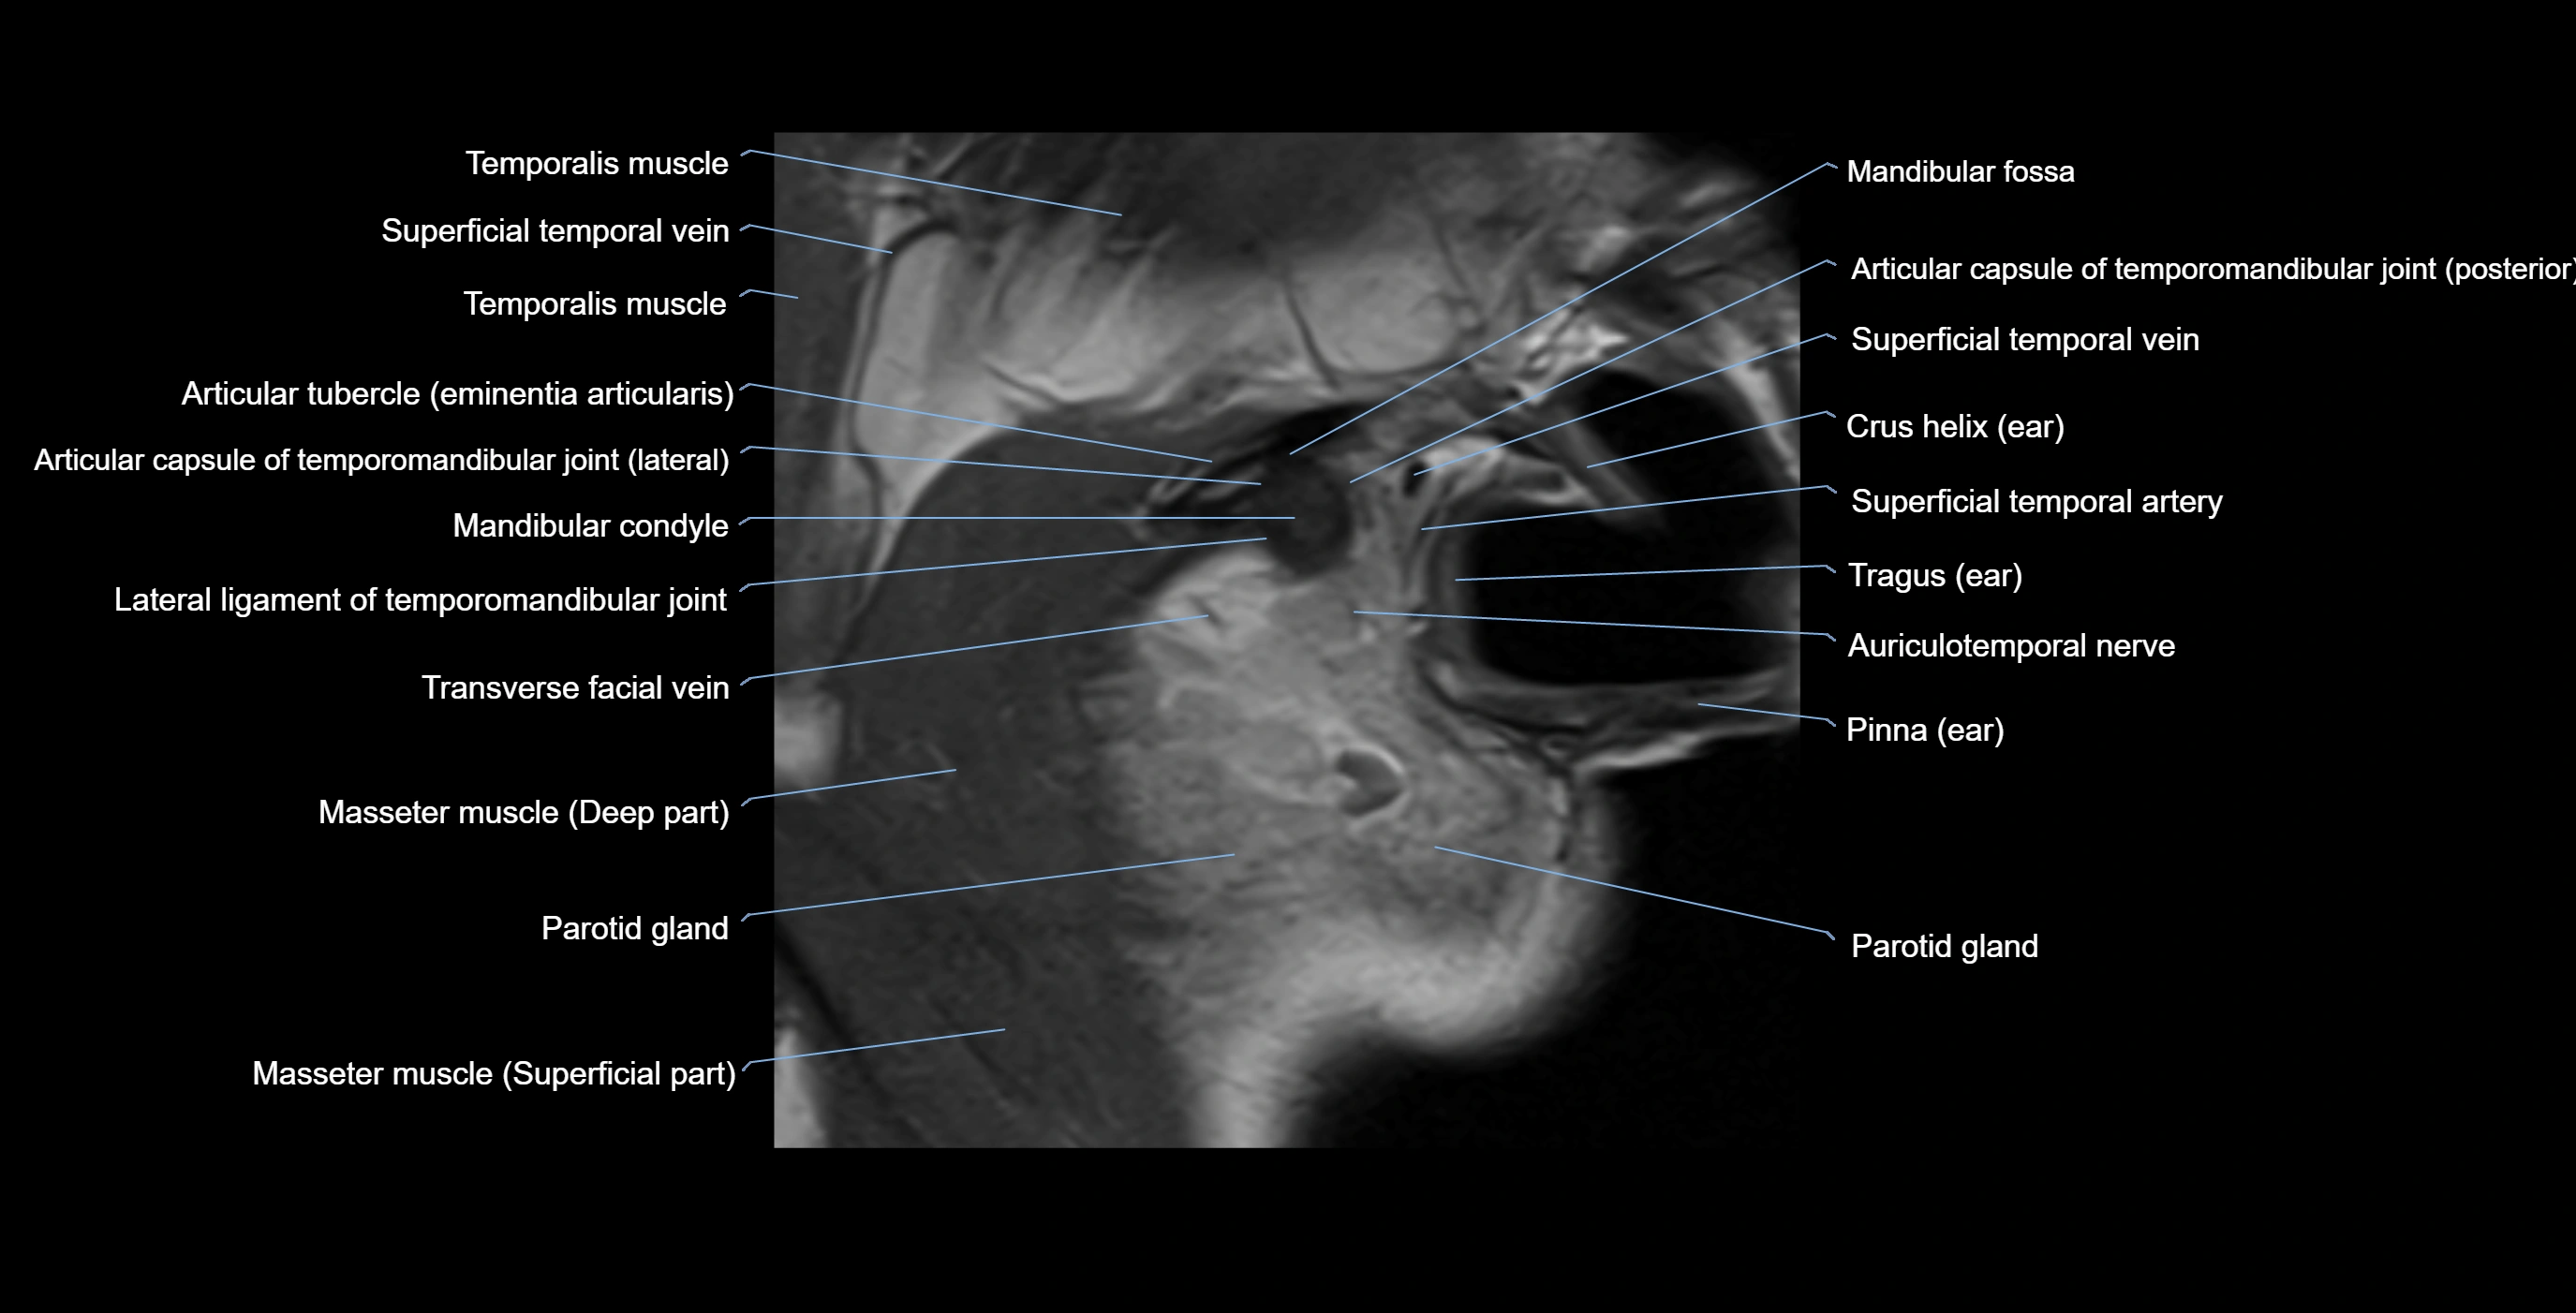

MRI appearance

T1-weighted images:

• Cortical bone: Low signal intensity

• Cancellous marrow: Intermediate to high signal depending on fatty content

• Teeth: Signal void structures

• Adjacent soft tissues: Normal gingiva and oral mucosa signal

T2-weighted images:

• Cortical bone and teeth: Low signal

• Marrow: Intermediate signal